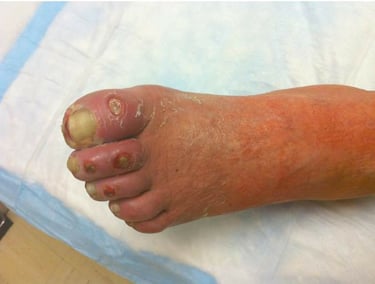

4. Diabetic foot ulcers (DFUs) and neuropathic wounds

People with diabetes commonly develop foot wounds because of peripheral neuropathy, foot deformities, repetitive pressure, and sometimes poor circulation. DFUs carry a higher risk of infection and limb loss than many other wounds, so early specialist involvement is often recommended. Management centers on debridement, offloading, infection control, vascular assessment, and optimizing blood glucose.